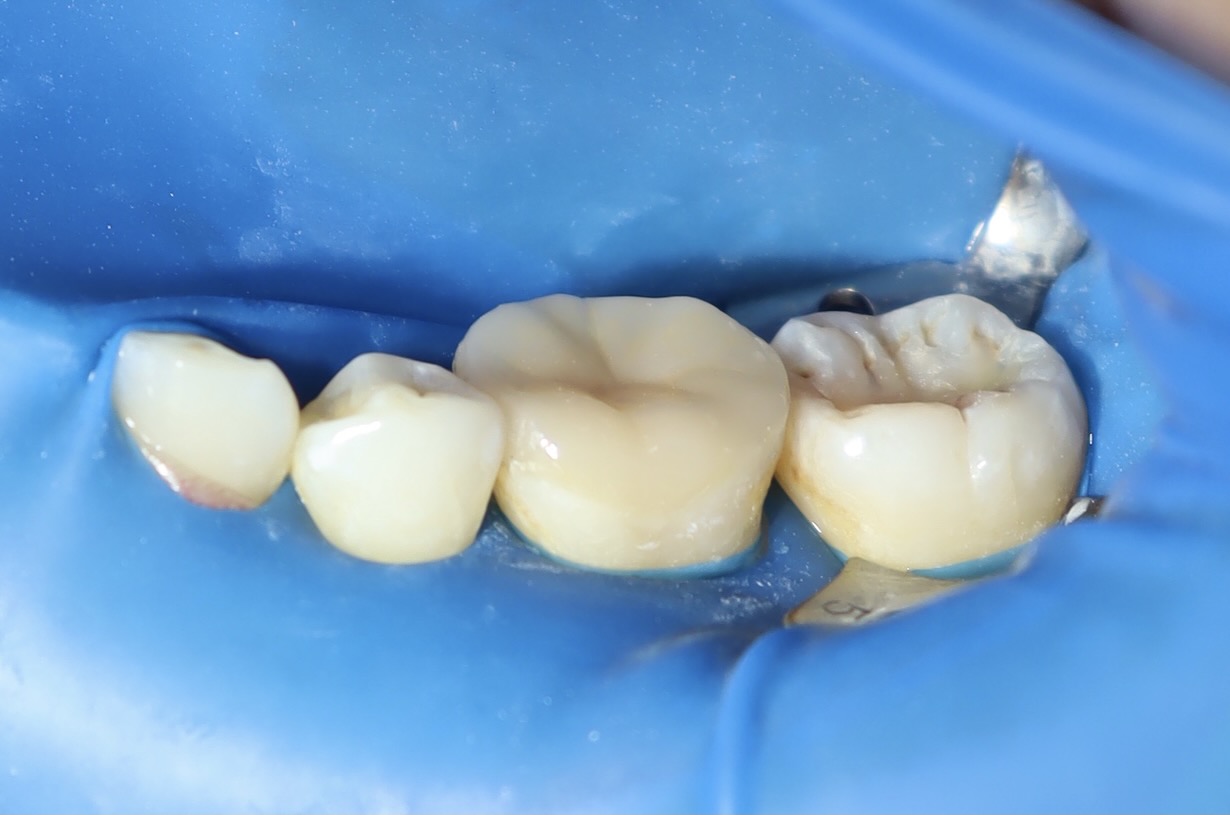

術後照片